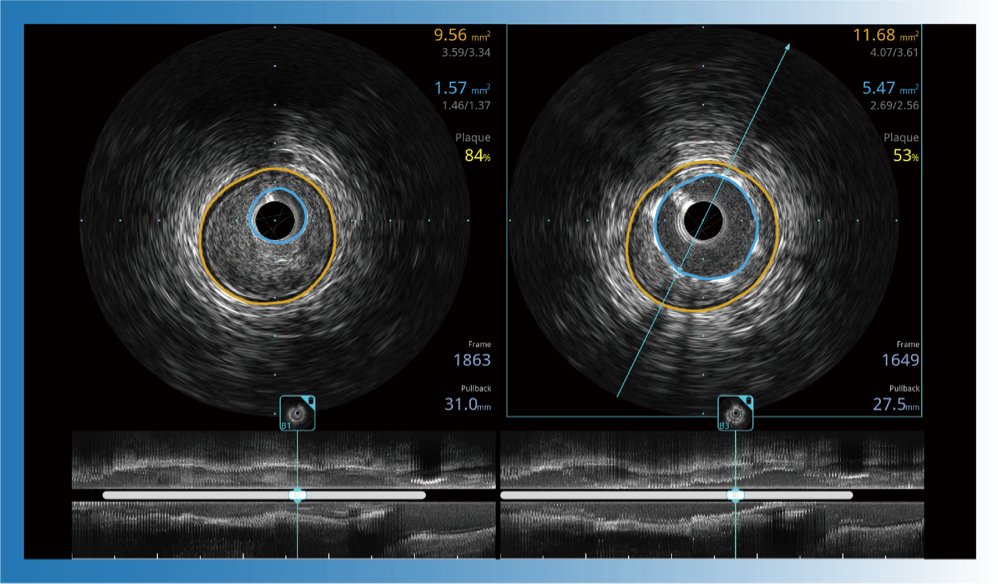

治疗前后两次测量录像对比

简化疗效评估

一键智能描迹,自动测量斑块负荷、面积狭窄率等指标,准确率高于90%